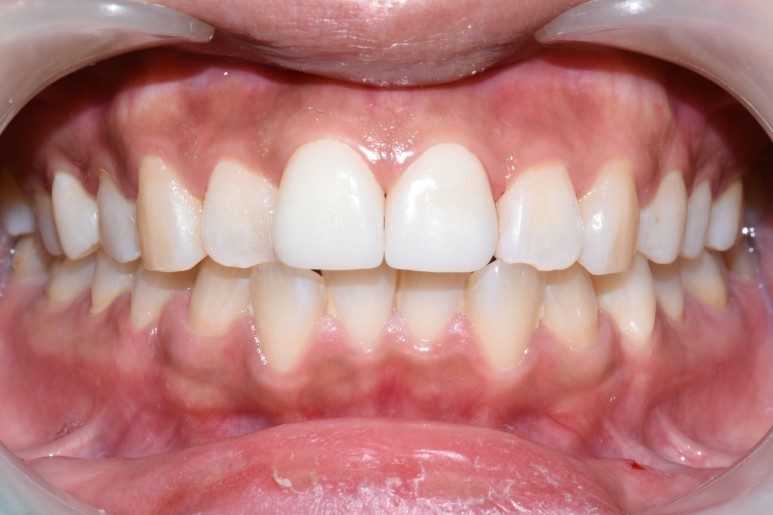

![[시청역/서울역 치과] 앞니 치아부러짐 자연스럽게 치료사례 관련 이미지 1](https://pub-9f2bb3498faf4d1d8714b41df24753e3.r2.dev/content/clinics/archive/rseeanjxfu/naver_blog/yonseiyegam/assets/by_hash/d423924e944a172afabe4390b46174eeeafc6704f921d50379a95cc08d5d4d36.jpg)

앞니가 깨져서 오셨을 때 처음 상태